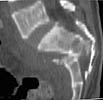

A 28 year old male jumped from the 4th floor on 11-25-2000 sustaining an L1 burst fracture that has been fixed anteriorly by the neurosurgeon with a strut between T12 and L2. A Kaneda device was placed anteriorly as well. My concern is the pelvic ring injury. There are bilateral sacral fractures through the foramen and a transverse element through the sacrum between S2 and S3. the lower part of the sacrum is displaced forward. Anteriorly there are right superior and inferior pubic rami fractures.

CT1